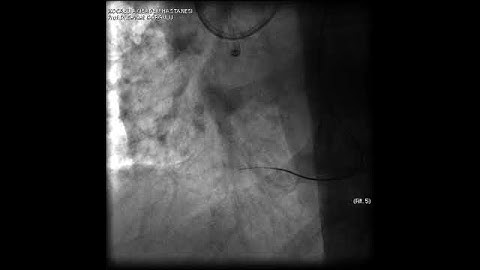

Aortic dissection and radial rupture during retrograde CTO PCI: Management of complications VİDEO 15